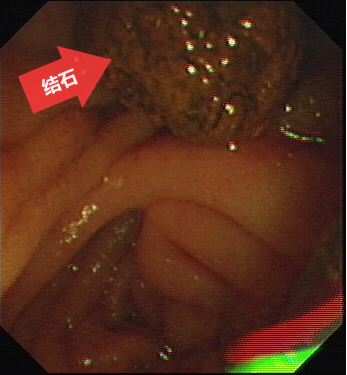

图五:结石(箭头所指)已取出至肠腔。

第五步:用取石网篮将结石从胆总管内取出到肠腔,通过肠道排出体外。